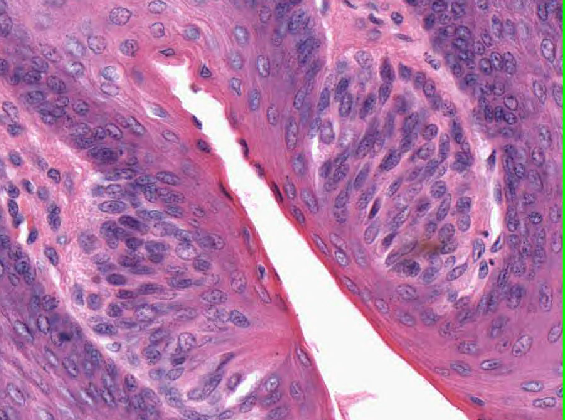

What is the arrow pointing to?

The abrupt transition between stratified squamous keratinising epithelium and non-keratinising epithelium